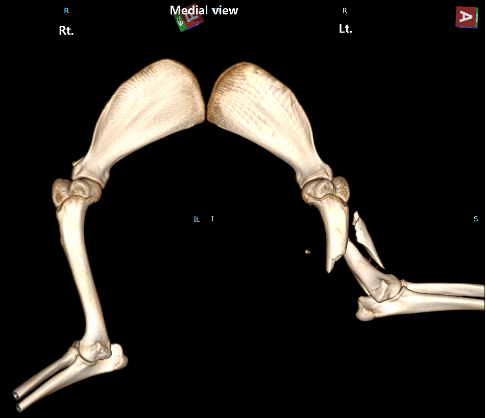

강아지 앞다리 상완골 골절 출처: 에스동물메디컬센터

02 영상 의학적 진단 결과

■ 상완골 분쇄 골절 (Lt. Humeral Comminuted Fracture)

왼쪽 앞다리 위쪽 뼈(상완골) 중간부터 원위부까지 뼈가 여러 조각으로 부서진 상태였습니다.

■ 골절 변위

가장 큰 골편이 앞쪽으로 심하게 이탈(Displacement) 되어 있었고 원위부 뼈들은 외측으로 밀려나 있는 복잡한 양상이었습니다.

■ 동반 골절

우측 제1, 2번 갈비뼈(Rib)와 경추 1번(Atlas) 날개 부위의 골절도 함께 확인되어 전신 충격이 상당했을 것으로 보였습니다.

CT 데이터를 기반으로 환자의 뼈 구조를 3차원으로 복원했습니다.